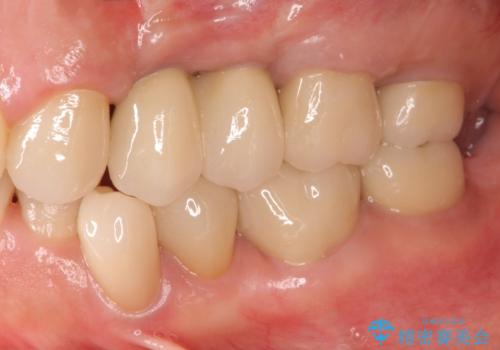

[メタルフリー] 虫歯・銀歯だらけの口腔内を全顎治療

![[メタルフリー] 虫歯・銀歯だらけの口腔内を全顎治療の症例 治療後](https://seimitsushinbi.jp/wp/wp-content/uploads/2025/03/530cf6cca6451bc106a9fb69dd58908a-500x350.jpg?v=1741918343)